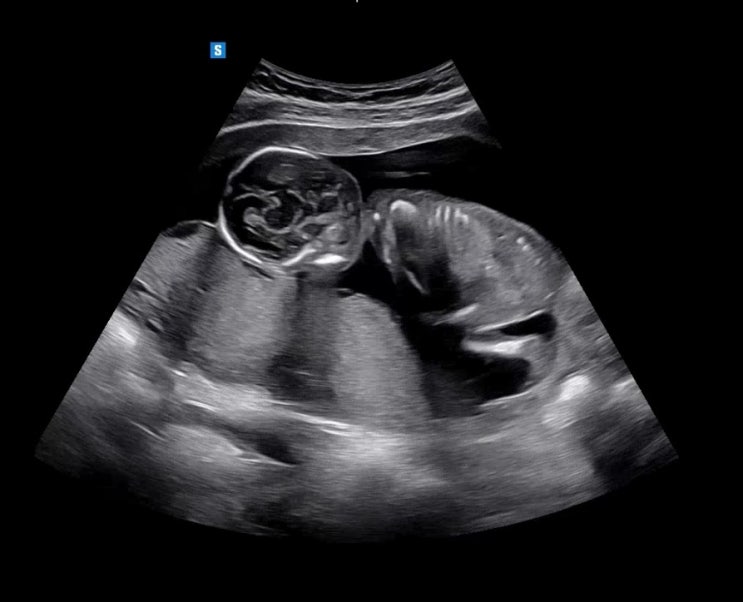

[초기] 임신 12주 ~ 15주(장꾸맘 각도법, 기형아 검사, 12주 정밀초음파, 입체초음파, 12주 각도법 성별예측, 입덧+체중변화, 스타벅스 수유등)

피고임 이슈가 9주차 검진에서 완전히 사라지고 조금 있던 입덧도 사라진 10주 이후 나는 컨디션이 아주 좋...